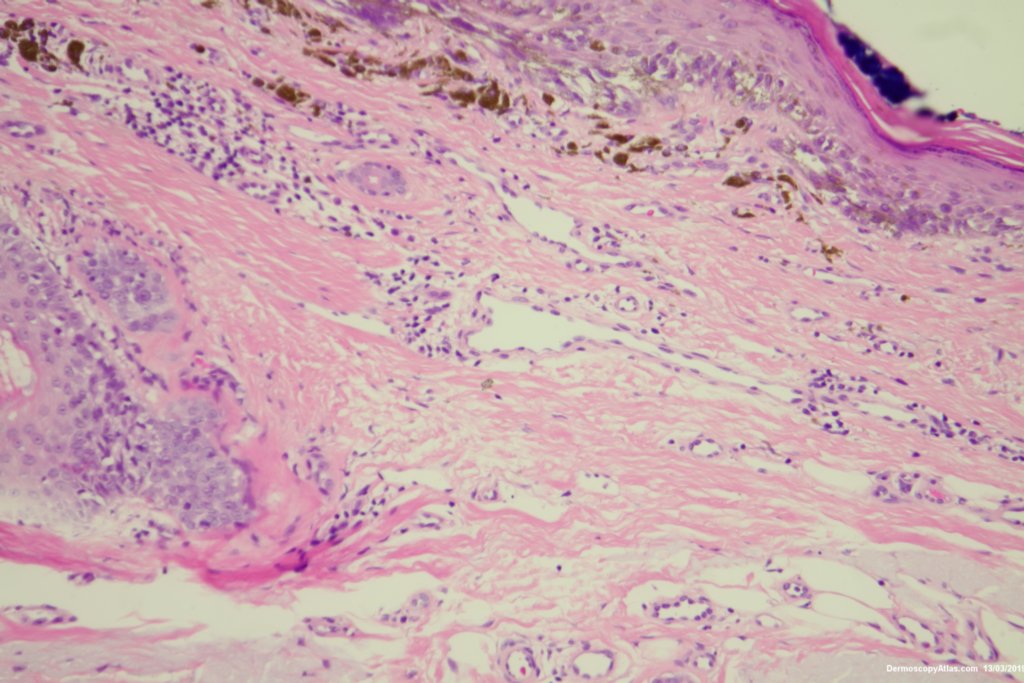

The histology was reported as an in situ melanoma with some dermal regression. It was excised with 5 mm clinical margins after the initial narrow excision biopsy.